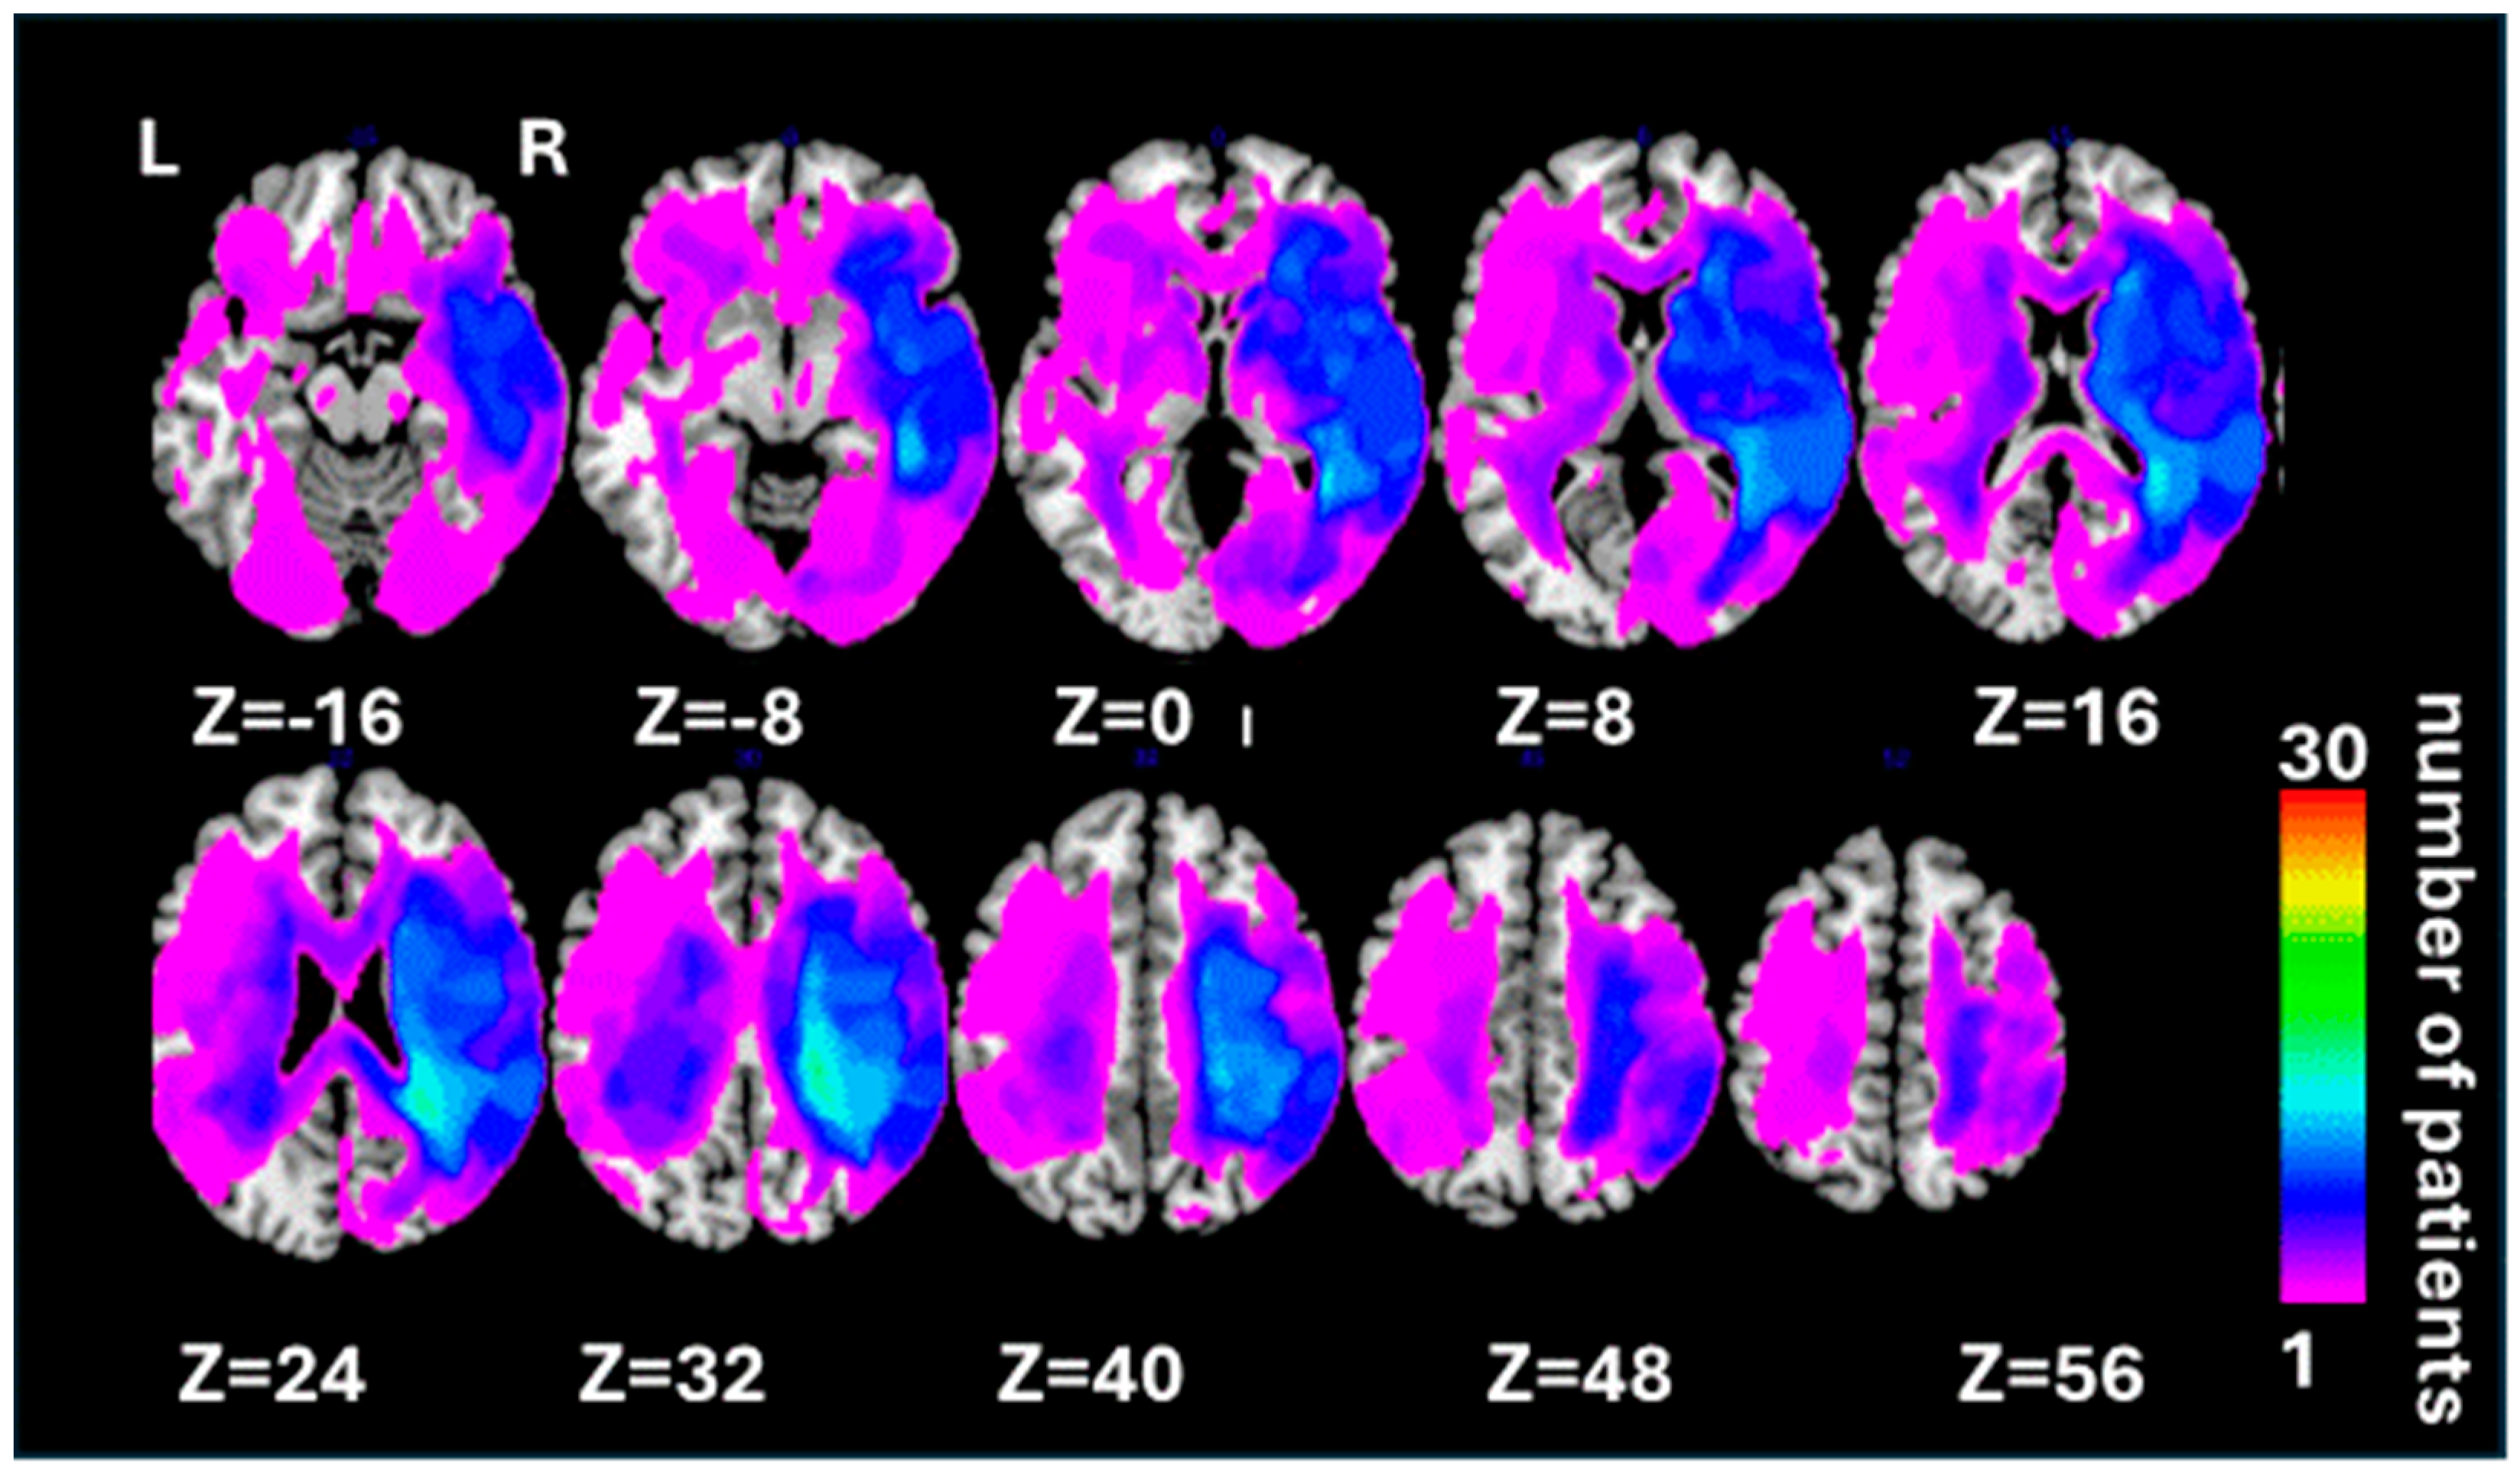

3.2. Neuroimaging Findings: Grey Matter Damage

3.3. Neuroimaging Findings: White Matter Disconnections